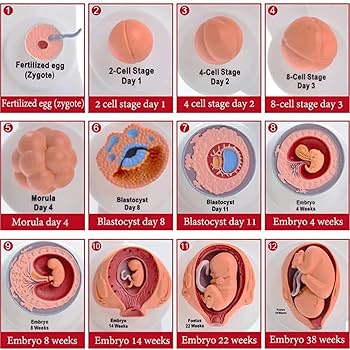

子宮内胎児の発育過程を示す L11 妊娠模型デラックスシリーズ。

Amazon.co.jp: Anatomy Stuff 出生前発達ポスター チャート 45x60cm、18x24インチ、胎児の成長図、妊娠成長チャート: ホーム&キッチン。

Amazon.co.jp : 胎児成長過程モデル 胎児モデル 胎児子宮胚発育モデル 医療教材 解剖学教材 : ホーム&キッチン。

Amazon.co.jp: 胚発生モデル 胎児の成長過程表示モデル 受精卵 ポピュラーサイエンスデモ用生物学教育モデル : 産業・研究開発用品。

Amazon.co.jp: 胎児発育モデル - 10ヶ月の胎児妊娠モデル - 胎児の成長および発達プロセスモデル 科学教育用の胚発育モデル :産業・研究開発用品。